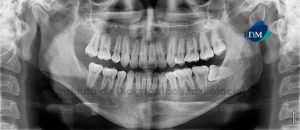

Paciente femenino, 55 años de edad acude al Instituto de Diagnóstico Maxilofacial (IDM) para su evaluación previo a tratamiento integral y colocación de implantes. A